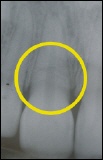

Wurzelbruch nach Sportunfall Das Röntgenbild zeigt die Bruchlinie in der Miitte des gelben Kreises als schwaze dünne Linie horizontal verlaufend.